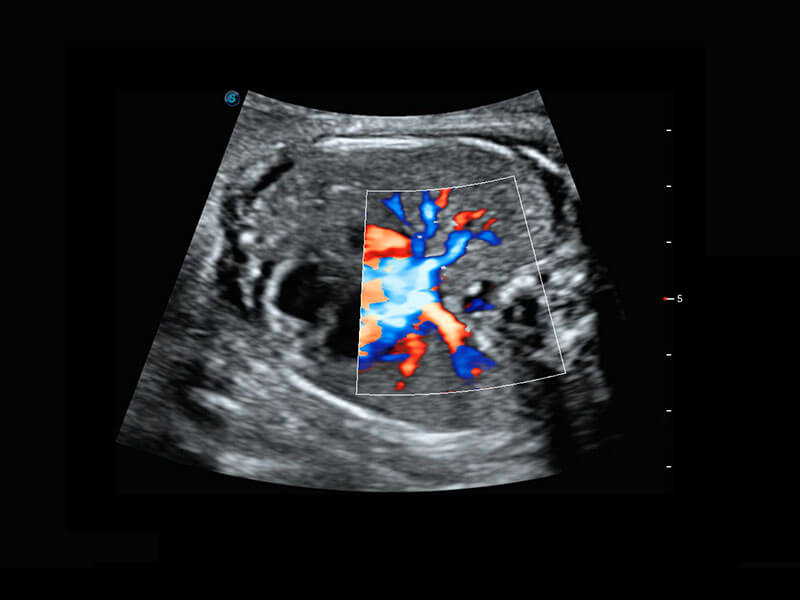

P60搭载一系列胎儿心脏成像技术,实现精细的胎儿心脏评估。

右室双出口